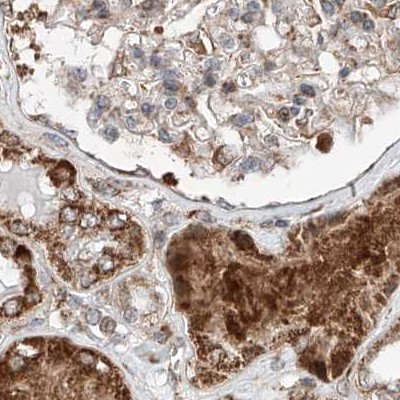

Immunohistochemical staining of human colon, kidney, liver and testis using Anti-ZSCAN29 antibody HPA011109 (A) shows similar protein distribution across tissues to independent antibody HPA007241 (B).